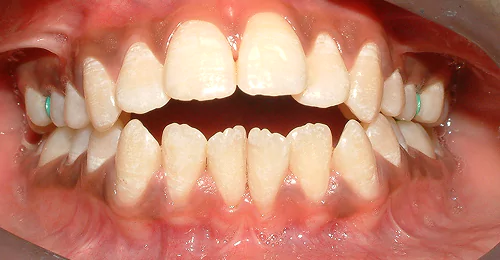

Anterior Crossbite Correction

Without Extraction Of Teeth

A young newly married female had crossbite in front teeth and when she smiled she felt her teeth appeared crooked. Being newly married she also had concerns regarding wearing braces. Assessing the situation, we advised ceramic braces and treated the condition without extracting or removing any teeth.

Pre Treatment

The treatment was completed successfully after a period of 18 months. Our patient is now embarked on her newly married life with more confidence.